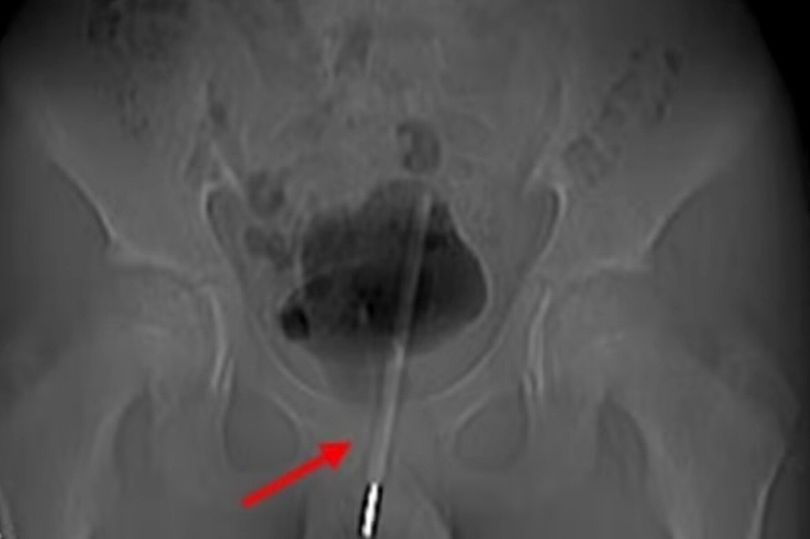

6. Termometer dalam Kandung Kemih

Termometer masuk ke dalam penis remaja laki-laki. Foto: Asian Journal of Surgery |

Kasus ini terjadi pada remaja laki-laki berusia 12 tahun di China. Adapun motifnya yaitu untuk masturbasi.

Hasil x-ray menunjukkan termometer tersangkut ke dalam kandung kemih melalui saluran kemihnya. Dokter memilih untuk mengangkat termometer itu menggunakan operasi lubang kunci.

Operasi ini dijelaskan lebih rinci oleh ahli urologi dalam jurnal Asian Journal of Surgery. Para peneliti mengatakan, mereka membuat lubang bedah kecil di jaringan ke kandung kemih, kemudian menggunakan alat kecil untuk menggerakkan termometer ke posisi yang benar untuk mencabutnya.

Operasi pengangkatan termometer tersebut dinilai berhasil. Terlepas dari itu, tidak ada kabar mengenai apakah remaja tersebut mengalami komplikasi imbas dari eksperimennya.